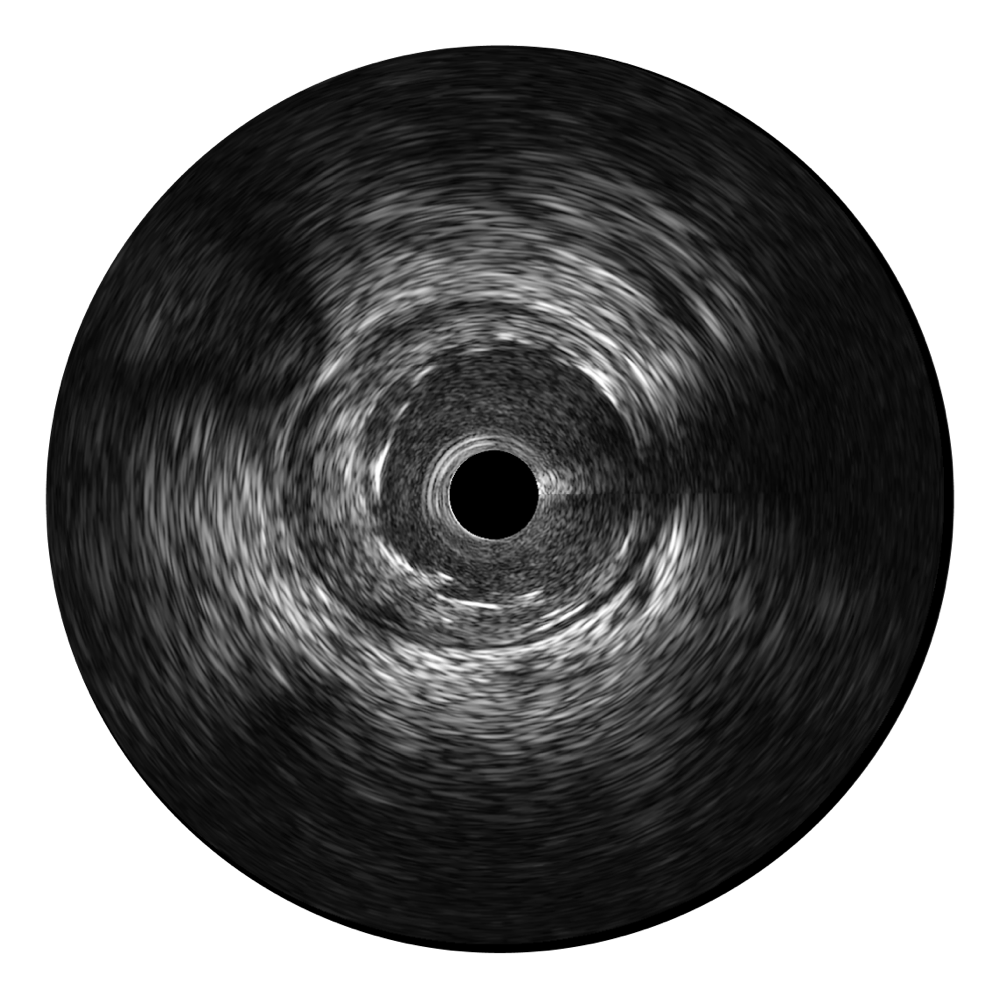

银河优越会超宽频成像技术覆盖20-80MHz1或20-90MHz2频率范围, 提供优异的分辨力同时也保证充足的穿透深度

对比传统IVUS导管成像,银河优越会宽频IVUS图像的近场支架梁显影更细腻,远场中膜外血管仍清晰可辨,兼顾远中近,兼顾分辨力与穿透深度